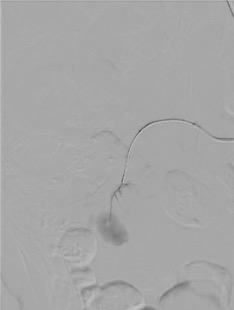

- Pseudoaneurysms: focal contrast pooling on angiogram; contained rupture of arterial wall — often at biopsy tract

Superselective Catheterization

Embolization

| Pseudoaneurysm / AVF | Coils (microcoils) | Superselective — coil across neck or feeding artery |